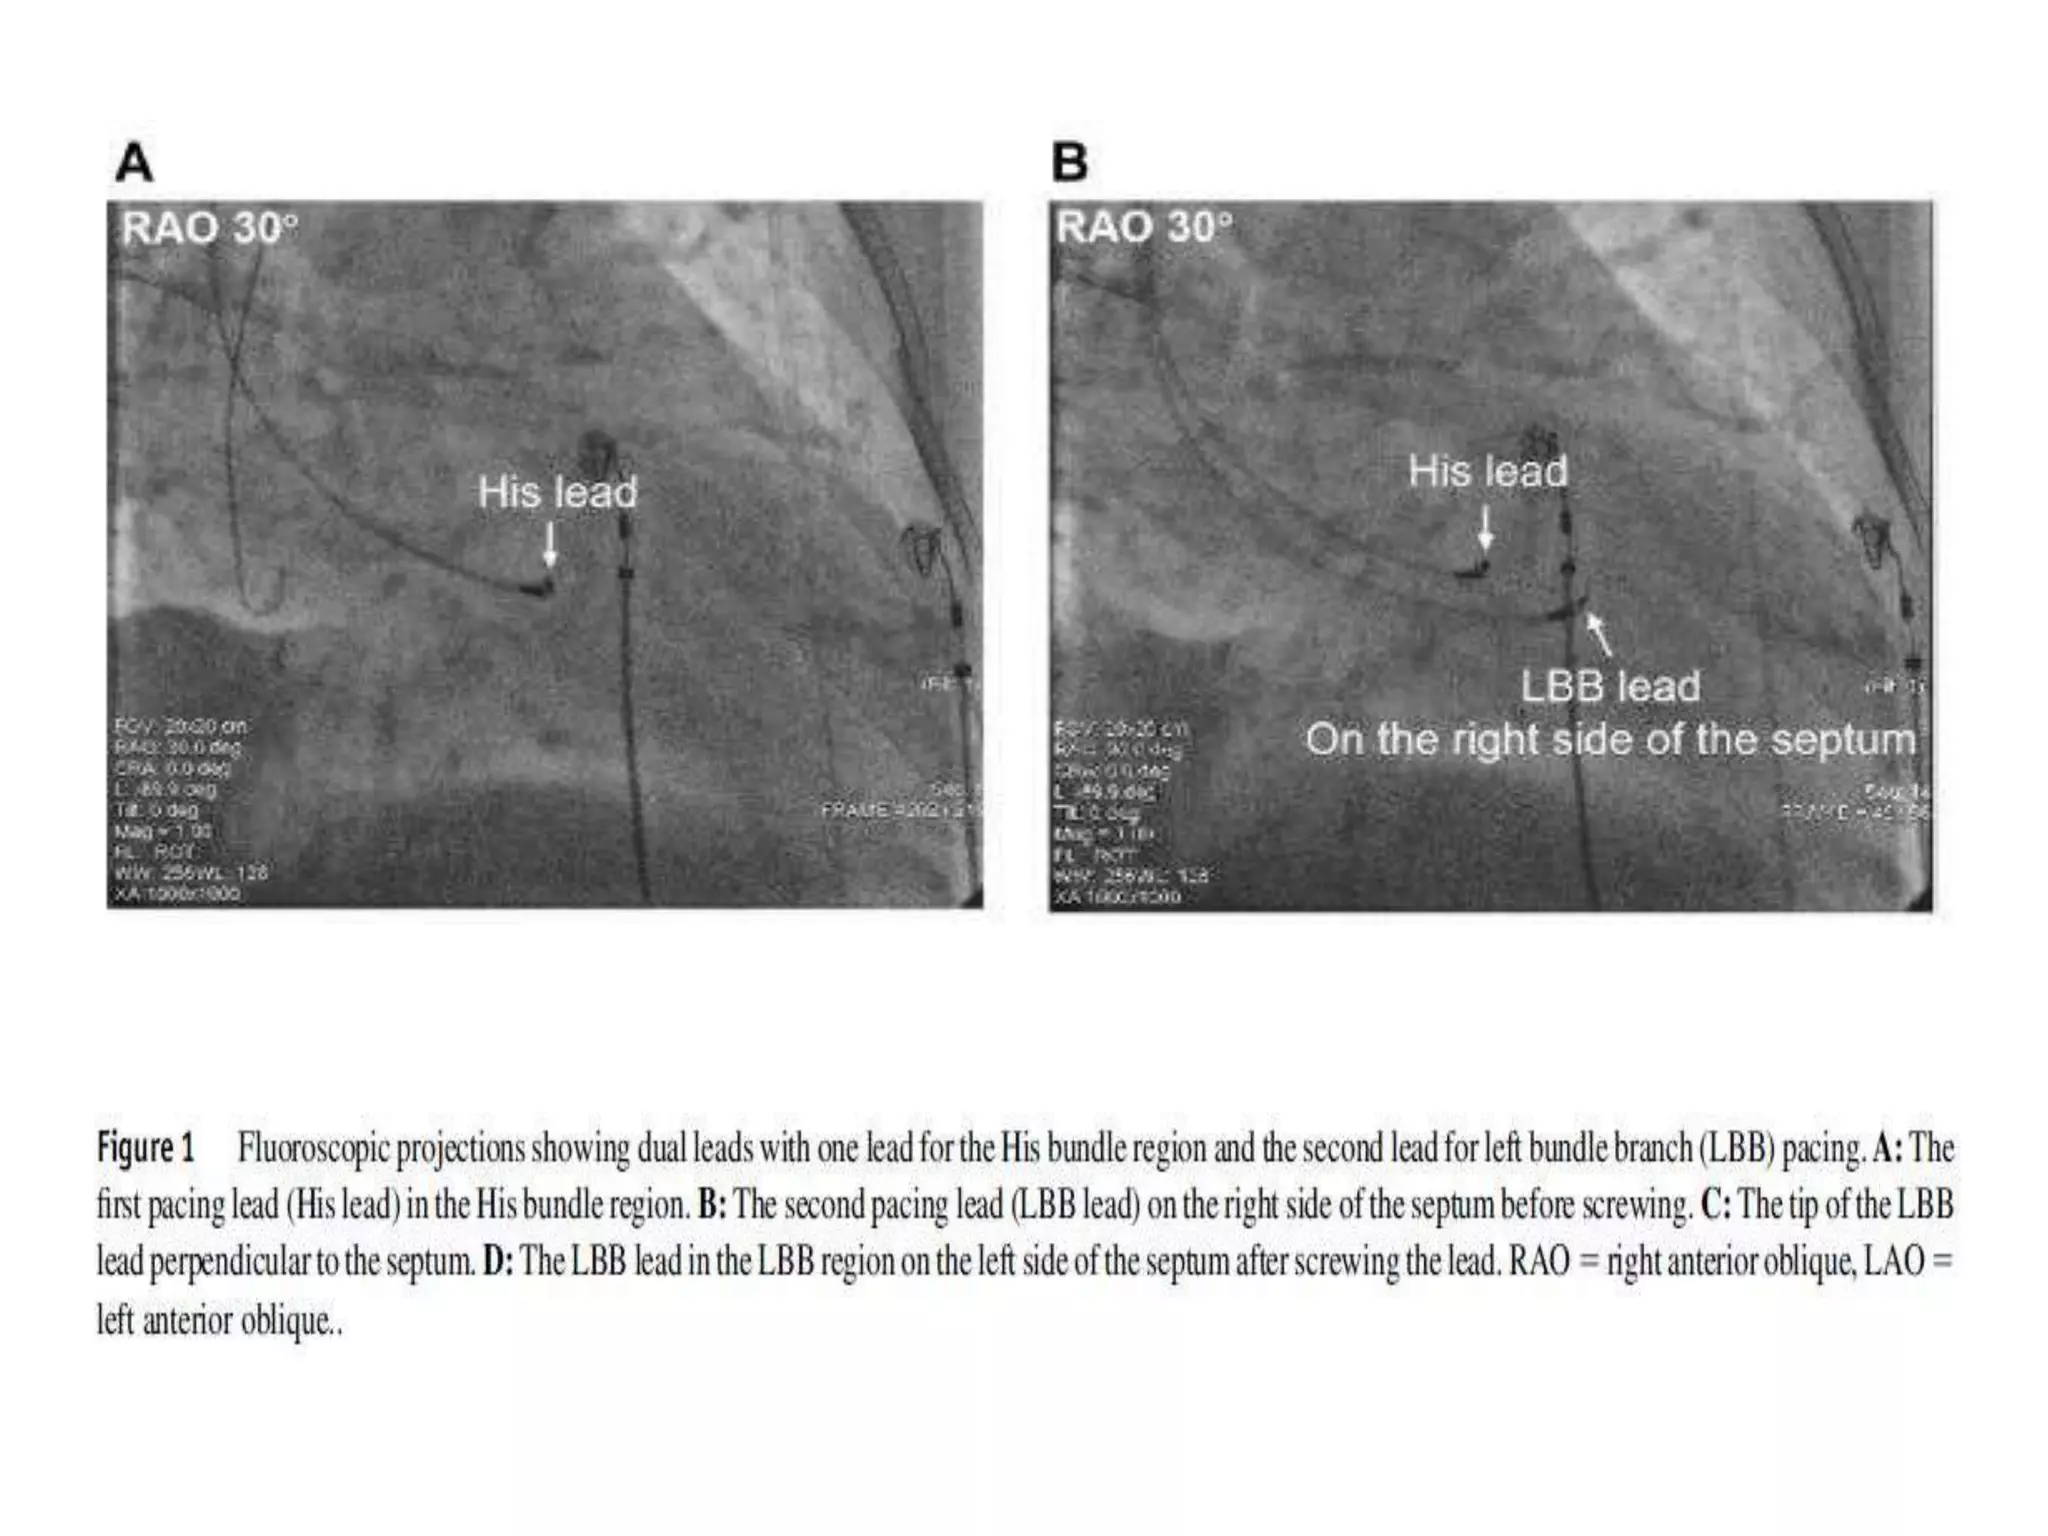

• The first technique uses the His bundle region

as an anatomical marker. Briefly, the delivery

sheath with the lead tip just beyond the distal

part of the sheath in the right anterior oblique

(RAO) 30 projection is first inserted into the

His bundle region where the His bundle

potential is recorded.

• The His bundle region is referred as a marker,

and the sheath with the lead is further

advanced toward the ventricular septum.

• Once the lead touches the right side of the

septum and the paced QRS morphology shows

ECG LBBB morphology during pacing with an

output of 5V/0.5 ms, the lead is pointed

toward the left side of the septum and

screwed in place.

• Once the paced QRS morphology shows right

bundle branch delay (RBBD; usually QR or rSR

in ECG lead V1/2) or near-normal QRS

complex, the lead advancement is stopped.

oblique (LAO) 30 projection.

• Then the lead is screwed toward the left side of

the septum in the RAO 30 projection. Once the

paced QRS morphology became RBB or near-

normal QRS complex, the lead advancement is

stopped.